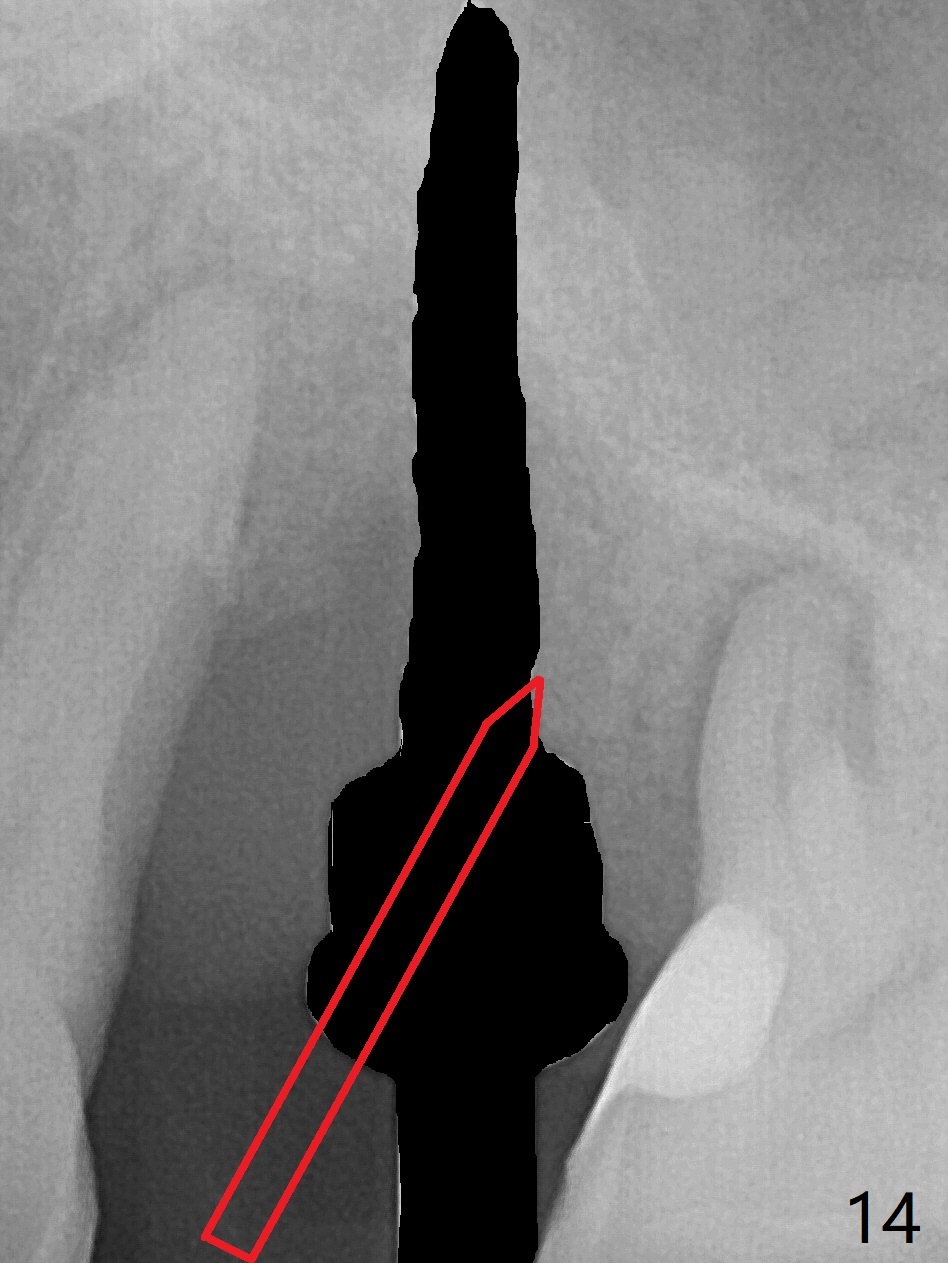

There is more bone apical to the residual root at #13 (Fig.1 red line). An immediate implant along the long axis of the root can be longer, 11.5 mm, favorable for primary stability (Fig.2 (CT taken immediately preop)). The initial trajectory is not ideal (Fig.3). When the pointed/Lindamann bur is removed (Fig.4), effort is made to move the apical end of the osteotomy distal (Fig.5 red arrow) by removing the apical bone (red dashed line). Following sequential osteotomy, a 4x10 mm dummy implant is placed with the trajectory remaining not so ideal (Fig.6,7). As the dummy implant is removed (Fig.8), a new osteotomy is established distal to the existing one (Fig.9). Subsequent drills gradually shift into the original osteotomy (Fig.10 red arrow). When the same dimension dummy implant returns, the trajectory improves with decreased stability (Fig.11). It seems reasonable to place a larger implant without further osteotomy. After placing PRF membrane and Vanilla graft for sinus lift (Fig.13 *), a 4.5x10 mm definitive implant is placed with loss of control in the trajectory (Fig.12,13).

When the initial osteotomy is off substantially (Fig.4), an osteotomy should be established de novo and as early as possible (Fig.14) so that subsequent osteotomy will not relapse to a great extent. More ideally, the initial osteotomy should be planned correctly (Fig.15,16) with sacrifice of the bone height. Nearly 1 month postop, the 4.5x5.5(5) cementation abutment is loose. When it is removed, the patient feels pain from the implant. A 5.5x6 mm healing abutment is placed instead. The implant osteointegrates with trabecular pattern in the sinus 9 months postop (Fig.20 *). The gingiva around the crown at #13 is healthy 1 year 4 months post cementation (Fig.18). Check the distal surface of #13 for bone loss if the tooth #14 is to be extracted.